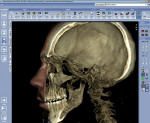

For example, the Planmeca ProMax 3D ProFace (Planmeca Oy, www.planmeca.com) can produce volume ranges to view a single tooth or the whole skull region. One imaging session can generate both a realistic 3-D photo (no radiation) and a CBVT volume. Lasers scan the face while a digital camera captures the facial images. The soft-tissue images can be overlaid on top of the cone beam images (Figure 1 and Figure 2), enabling the clinician to visualize the soft tissue in relation to the facial bones and teeth, making treatment planning easier and improving esthetic results. This imaging is available in Europe but has not yet received FDA clearance for use in the United States.